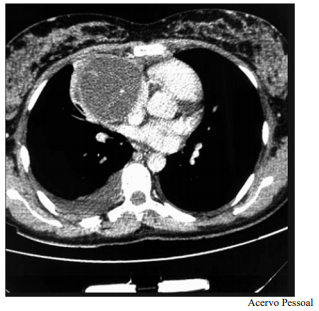

Um paciente de 17 anos de idade revela idas frequentes à emergência por causa de tosse e dispneia. Em exame de imagem investigatório, identificou-se, na tomografia computadorizada de tórax (TCT), uma massa mediastinal anterior bem definida, com densidade de partes moles, medindo cerca de 17 cm x 11 cm x 10 cm, conforme representado na imagem a seguir. A lesão não invadia estruturas adjacentes, e não foram encontradas outras alterações nas tomografias de tórax, de crânio e de abdome. Foi realizada uma biópsia pré-operatória guiada por TCT, cujo diagnóstico foi compatível com teratoma de mediastino.

Considerando esse caso clínico, a imagem apresentada e os conhecimentos médicos correlatos, julgue o item a seguir.

As massas do mediastino anterior têm, como principais etiologias, os timomas, os linfomas, os tumores de células germinativas e os tumores da tireoide.